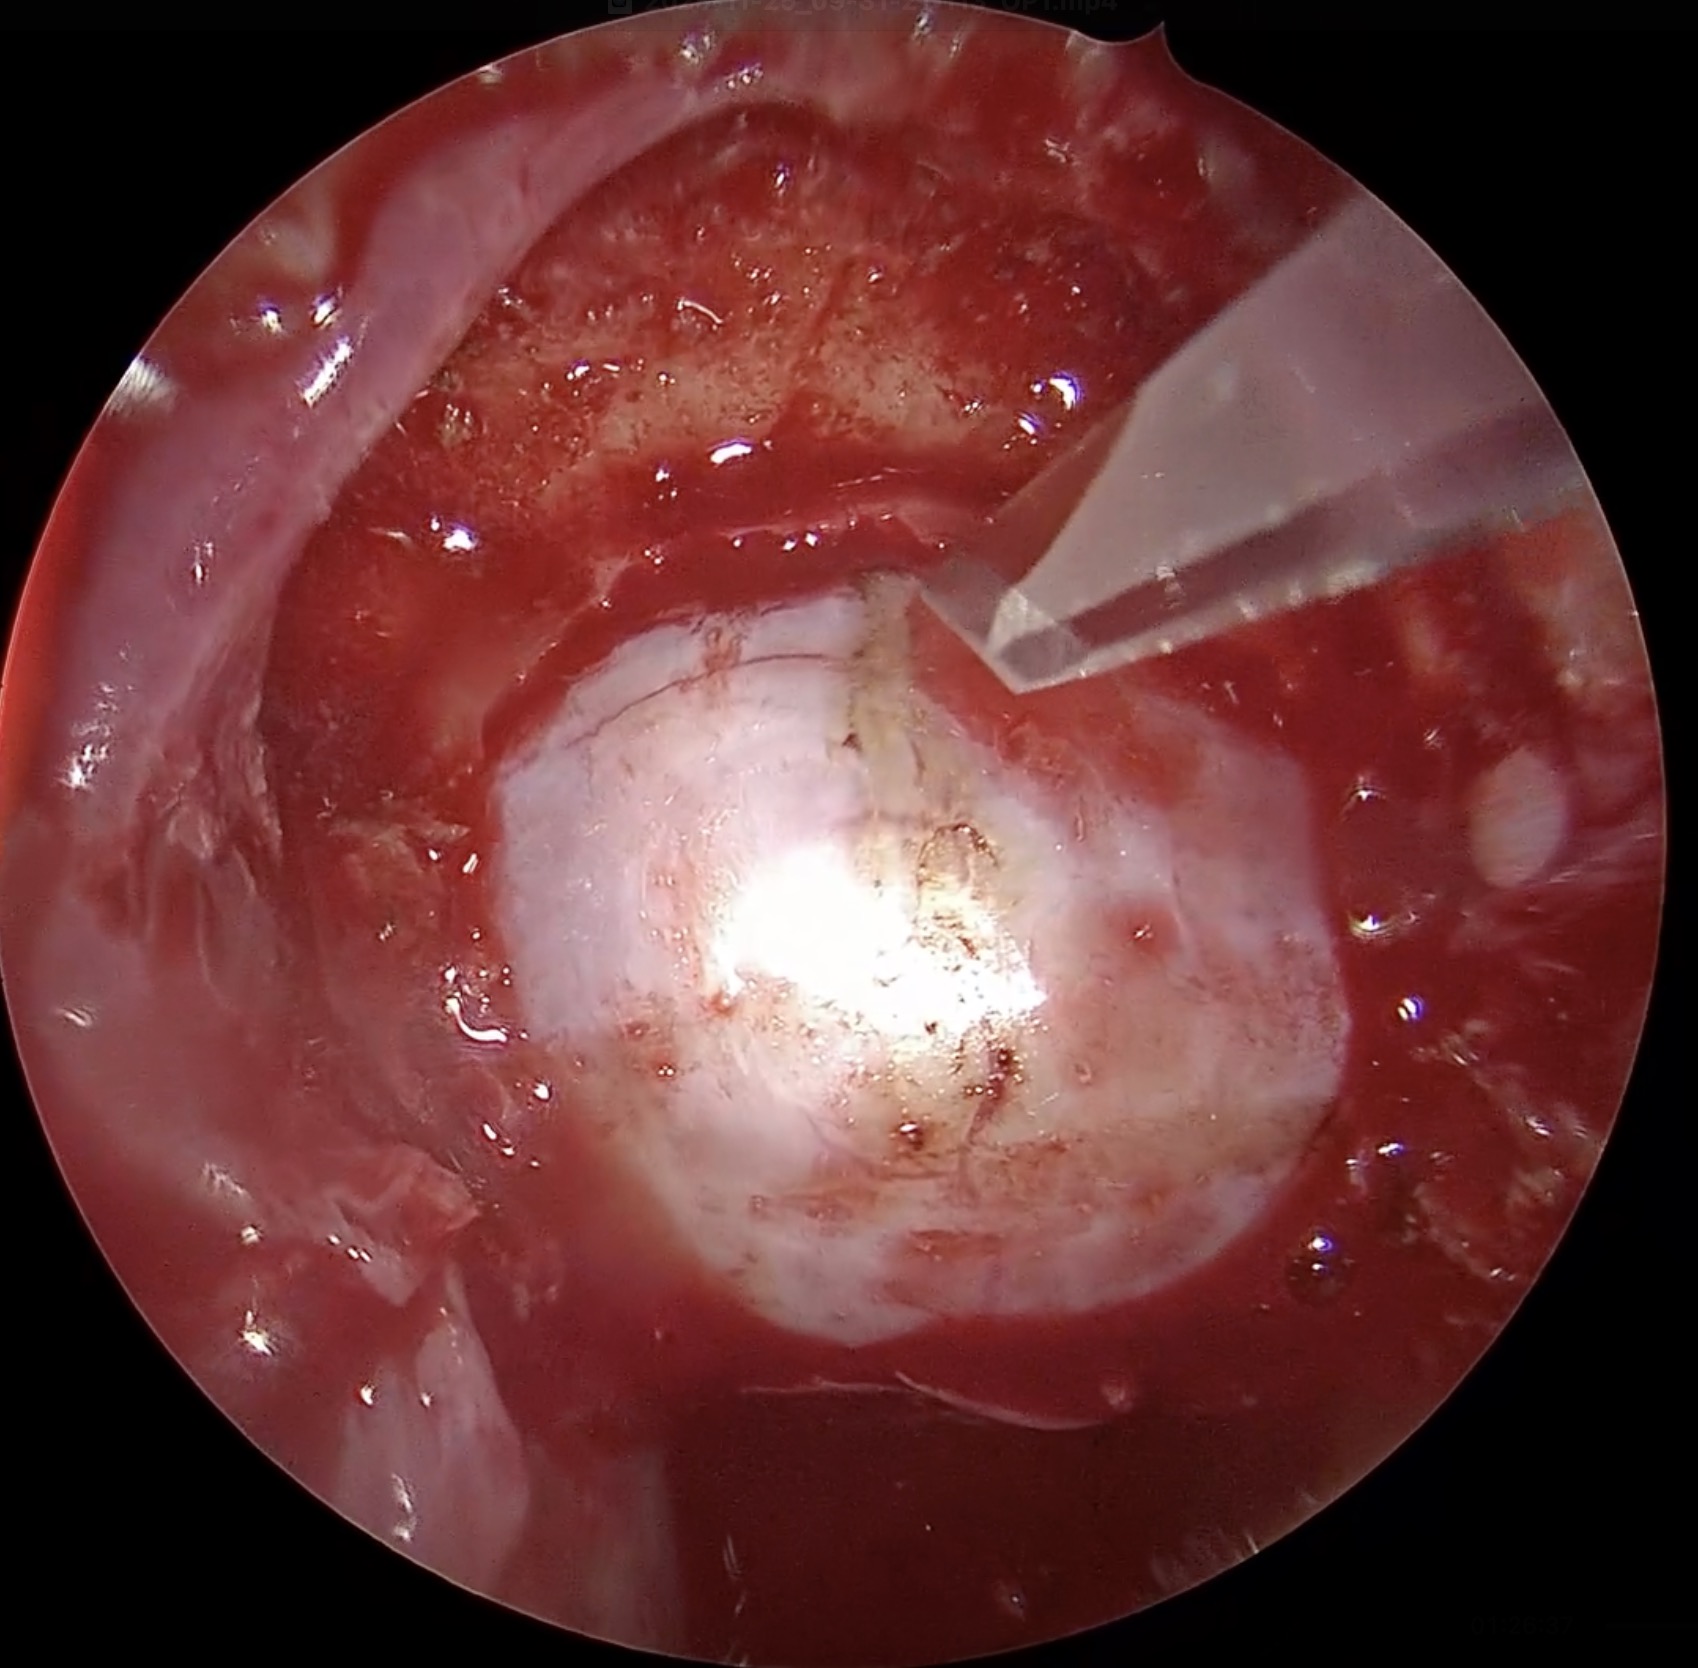

37歳女性 下垂体線腫を内視鏡手術しました。両耳側の視野欠損が回復しました。

若いですが、視野狭窄で発見された下垂体線腫を内視鏡で摘出しました。トルコ鞍前壁を十分に削除することで、上方の腫瘍残存をなくし、術後出血を防止できました。一過性に尿崩症が出現しましたが、コントロールされ退院されました。